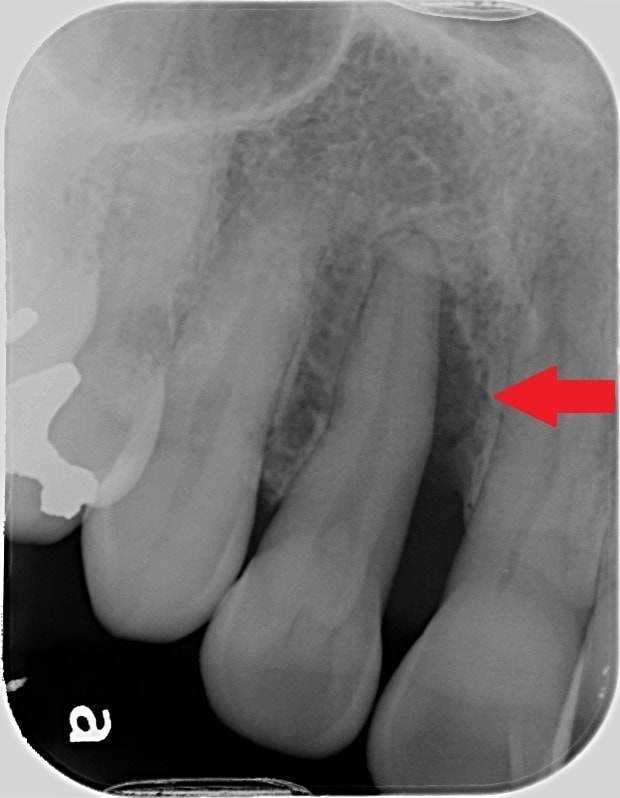

治療前は、赤の矢印で示すように歯の周りに黒いところがあることが分かるかと思います。簡単に言うと、骨が溶けた状態になります。

通常、歯周ポケットと呼ばれる歯と歯茎の間の溝は3㎜程度なのですが、10㎜を超える歯周ポケットがありました。CTは、手術前に骨の欠損形態を的確に把握できるため、歯周病の治療にも非常に有用です。

歯周病の基本的な治療を行い、その後に、歯周組織再生療法という失われた歯の周りの組織を再生させる手術を行って約2年のレントゲンになります。

青の矢印で示すように、治療前黒かった部分が、白くなってきていることが分かるかと思います。失われた歯周組織の再生が促されていることが推測されます。CTにおいても歯の周囲の失われた骨が再生してきていることが、分かるかと思います。

初診時のレントゲンで、赤の矢印が示す黒いところは、簡単に言うと歯周病で歯の周りの骨が溶けてしまっている状態です。

歯周組織再生療法という歯の周りの骨の再生を促す手術後2年6ヶ月後のレントゲンでは、緑の矢印で示すように、黒かったところが白く変わっていることが分かるかと思います。溶けてしまっていた骨の再生が、促されていることが推測されます。